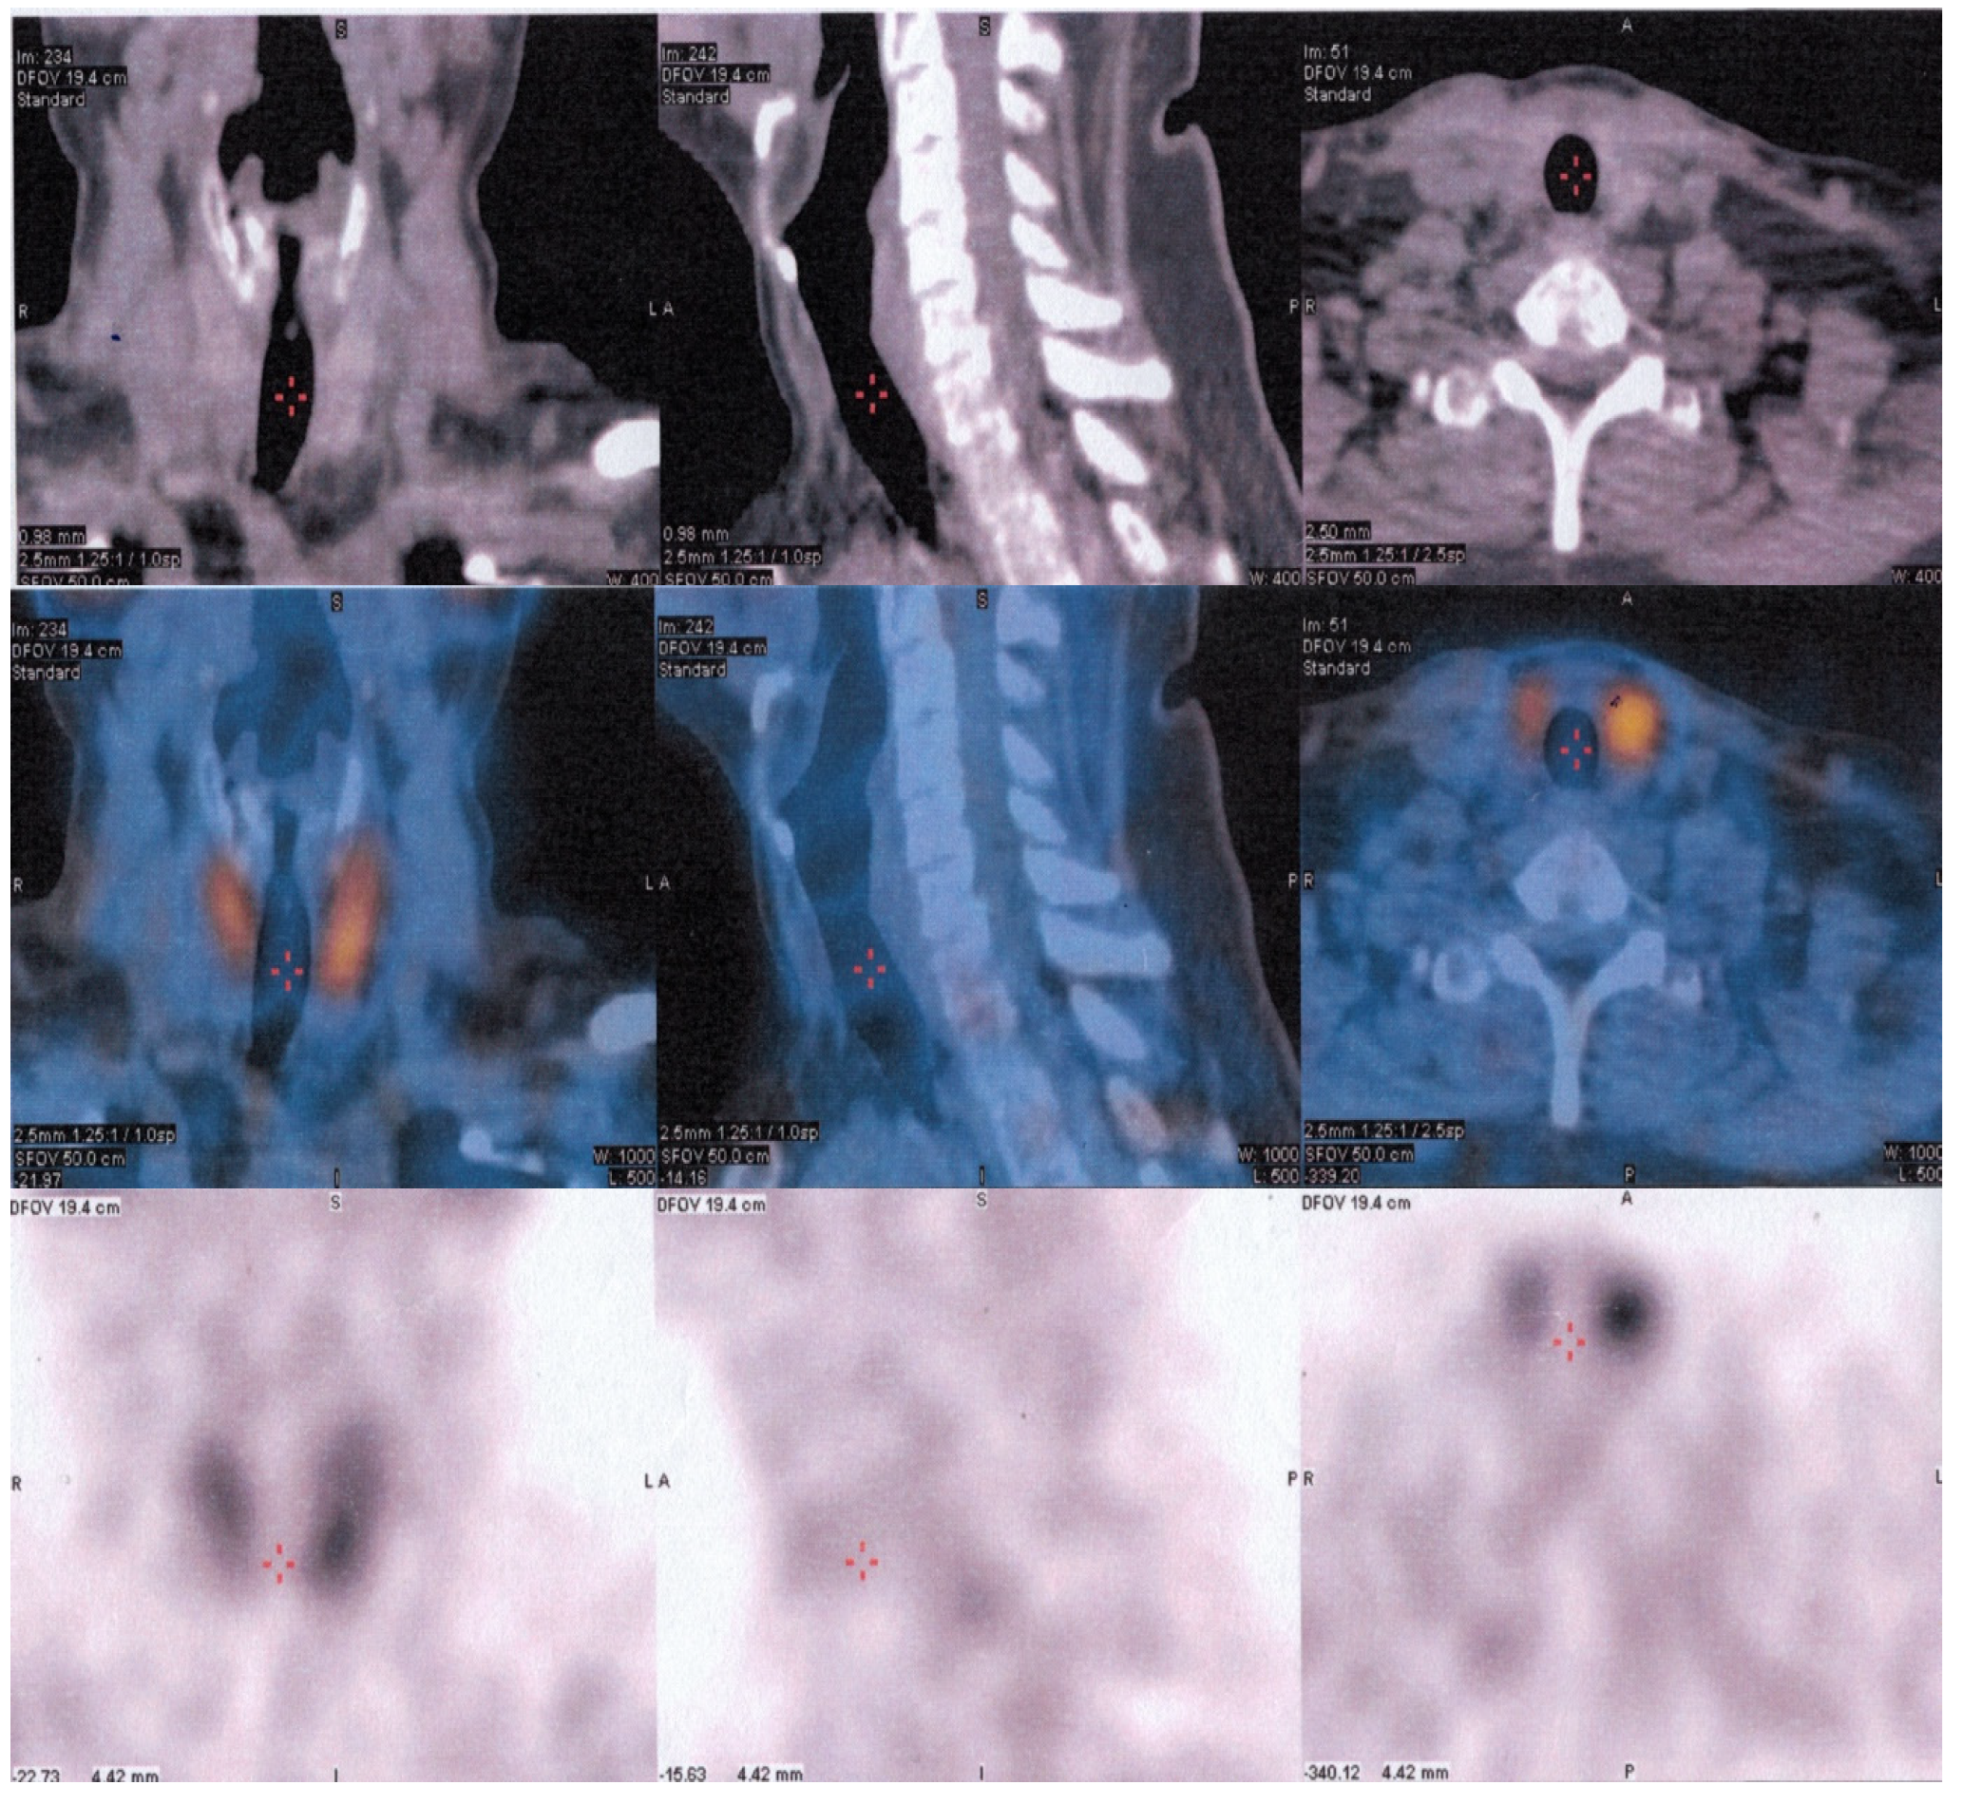

Considering the pathology results, which indicated parathyroid carcinoma, the recommendation for the patient was external radiation therapy instead of another surgical intervention. Subsequent SPECT/CT combined with 99mTc-sestamibi scanning imaging revealed no abnormal parathyroid lesions, including ectopic locations (Figure 4). A comprehensive follow-up care plan has been established to closely monitor the patient and mitigate the risk of any potential complications.

Figure 4.

SPECT/CT combined with 99mTc-sestamibi scan without any abnormal parathyroid lesions, including in ectopic locations.